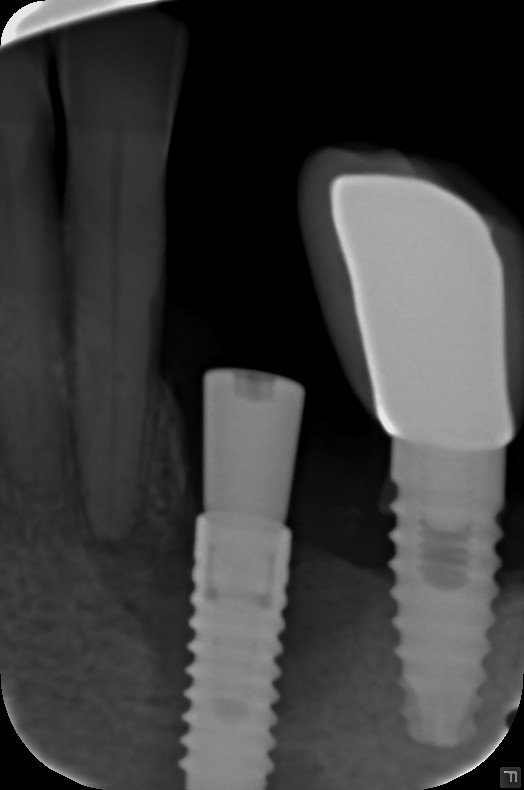

Los implantes de 17 y 27

Buenos días Paciente que acude a consulta con fracaso de implantes a la altura de 15-13 y 22. Los Implante de 17 y 27 los podemos conservar, pero no tenemos [...]